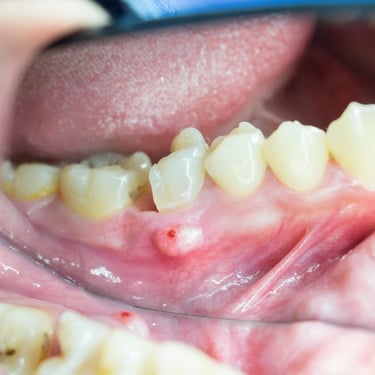

Absceso Periapical Crónico

Un absceso periapical crónico es una infección prolongada en la punta de la raíz del diente que forma una bolsa de pus.

Los pacientes pueden tener dolor leve o no tener síntomas, pero notar una fístula en la encía.

El tratamiento incluye un tratamiento de conducto y, en algunos casos, una cirugía apical. Es crucial tratarlo para evitar la propagación de la infección.